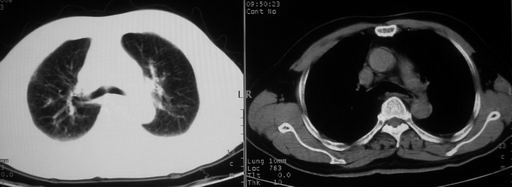

男,78岁,咳嗽、咳痰、发热入院,抗炎治疗一周后已退热,咳血似痰。

10月3日片: